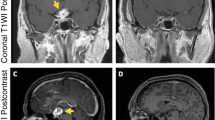

Bošnjak and Benedičič [14, 15, 50] evaluated the feasibility and utility of recording scalp VEP responses to direct electrical stimulation (eVEP) of the ON during tumor removal surgery involving the anterior visual optic pathways [14], skull base [15], and during orbital enucleation due to malignant melanoma of the choroid or the ciliary body [91]. To acquire cortical potentials elicited by electrical epidural stimulation of the optic nerve (ON), insulated platinum needle-stimulating electrodes with a noninsulated ball tip were attached epidurally to both sides of the ON. Bošnjak et al. [50] used the following procedure for placement of these electrodes, noting that “When the exit of the optic nerve (ON) from the periorbit is fully visualized through a small fenestration of the orbital apex, needle electrodes are placed in contact on each side of the ON into the cleft between the nerve itself and the basal remnants of the lateral walls of the optic canal. The needles are manipulated during positioning with bipolar forceps through grip connectors. After placing the epidural stimulating electrodes , their position is secured with wet cotton patties laid over the orbital apex and leads.” Monopolar optic nerve potentials after retinal flash or electrical epidural stimulation of the ON were then recorded with insulated platinum ball-tipped wire electrodes placed on the surface of the ON using an extracephalic reference electrode. The distance between the stimulating and recording electrodes was approximately 25 mm. The same recording electrodes were used for monopolar recordings from structures outside of the visual pathway to collect control data. The electrical stimulus consisted of a rectangular current pulse of varying intensity (0.2–5.0 mA) and duration (0.1–0.3 ms) using a stimulation rate of 2 Hz [14, 15]. The bandpass filter settings utilized in previous studies were 1–1000 Hz when recording these cortical potentials after electrical epidural stimulation of the ON. The analysis time used was between 10 and 300 ms. Each trace was generated from the average of 100 responses. Of note, considerable stimulus-related artifact from direct ON stimulation does present a technical hurdle to recording these potentials [14, 15]. Using this stimulation and recording technique, Benedičič and Bošnjak [14, 15] concluded that it was beneficial in preventing ON damage and improving outcomes. They did not report any warning criteria used in the studies and their sample sizes were small [4]. The typical eVEP they recorded consisted of N20 and N40 waves (Fig. 4.3) [50]. Considerable variability in the amplitude of the responses was observed (e.g., N40 wave amplitudes prior to tumor removal varied as much as 25 %). Not surprisingly, artifact was observed with use of bipolar coagulation, ultrasonic aspirator, laser, and craniotome-hampered IOM [15]. In one patient with an ON sheath meningioma and vision limited to light sensation, only the N20 wave was observed (see Fig. 4.3) [50]. In their subsequent report of IOM monitoring for a very small sample (N = 3) of patients undergoing orbital enucleation due to malignant melanoma of the choroid or the ciliary body, both F-VEPS and cortical potentials from direct stimulation of the optic nerve were inconsistent or absent in patients with a history (>3 months) of severe visual deterioration, but obtainable from a single patient with a short history of mild visual impairment [91]. Clearly, more studies are needed to confirm the utility of direct electrical stimulation of the optic nerve for visual pathway IOM use and for the development of effective preoperative criteria for patients in whom these techniques may be useful, as well as warning criteria that correlates with and improves patient outcomes.

(a) An example of a typical electrically elicited visual-evoked potential (eVEP) response is depicted. The response consists of a larger N20 wave and a smaller N40 wave. The stimulus duration was 0.5 ms, and its frequency 2 Hz. An average of 100 responses was obtained. (b) The eVEP responses recorded from a patient with an optic nerve sheath meningioma and visual perception of light only is shown for which a decreased N20 wave and absent N40 wave are observed (from Bošnjak and Benedičič [50]; with permission)